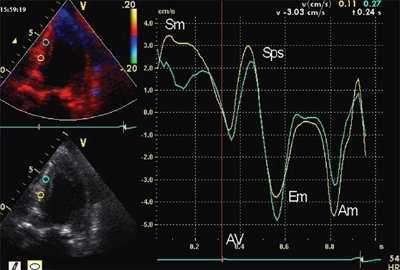

На рис. 1-5 представлены примеры проведения количественного анализа SQ (Strain quantification) тканевого допплеровского изображения в программе Q-lab 3.0. Принцип выделения изоволюмических фаз демонстрируется на рис. 1. Принцип количественного анализа деформации (ε) сегментов миокарда представлен на рис. 2-3, скорости деформации (SR) - на рис. 4, графиков SR/(ε) - на рис. 5.

![Пример определения длительности изоволюмических фаз при постобработке данных тканевого допплеровского исследования у пациента с выраженной ГЛЖ]()

Рис. 1. Пример определения длительности изоволюмических фаз при постобработке данных тканевого допплеровского исследования у пациента с выраженной ГЛЖ.